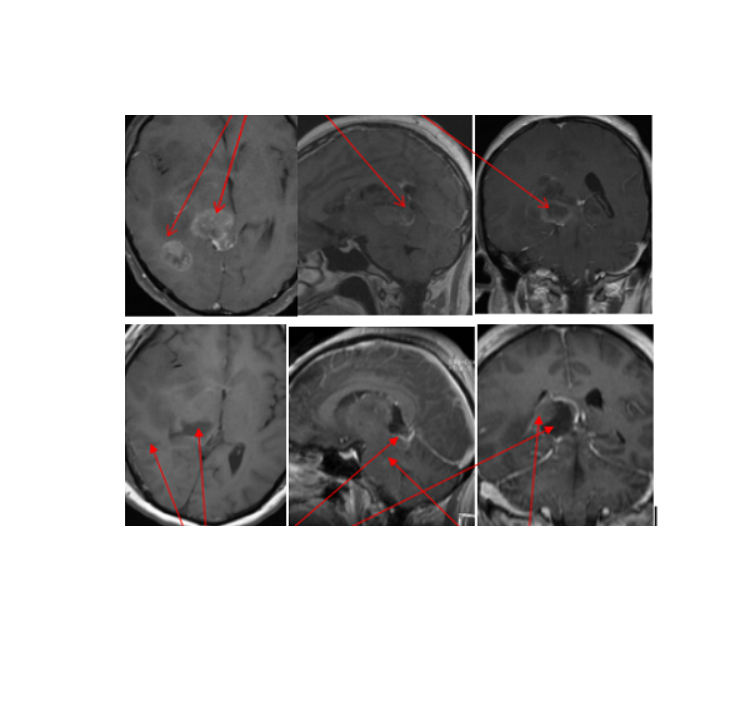

案例3:小听(化名),20岁,脑干胶质瘤,在INC帮助下,在德国肿瘤占位全切术后一天患者清醒,可正常对答。术后一个月,自行步行出院,未再有癫痫发作。

虽然脑瘤的确可怕,但并非全部脑瘤都是传统印象中的不治之症,在国际专家手下,被治愈的机会是大的,所以患者不要放弃希望。为了国内的患者能更容易获得国际水平的治疗,INC还开设了国际远程咨询服务,患者不出国门就能与教授教授面对面咨询,获得他们可靠的独特见解。而对于有出国看病打算的患者,提前做一次咨询,再确定是否要出国,可以节省就医时间和费用。